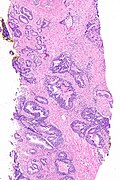

Small cell carcinoma of the prostate. H&E stain. | |

Microscopic

Features:

- Small cells with:

- Nuclear moulding.

- Stippled chromatin.

- High NC ratio.

- +/-High-grade acinar adenocarcinoma, i.e. conventional prostate carcinoma, seen in ~50% of cases.[1]

Notes:

- Similar to small cell carcinoma of the lung.